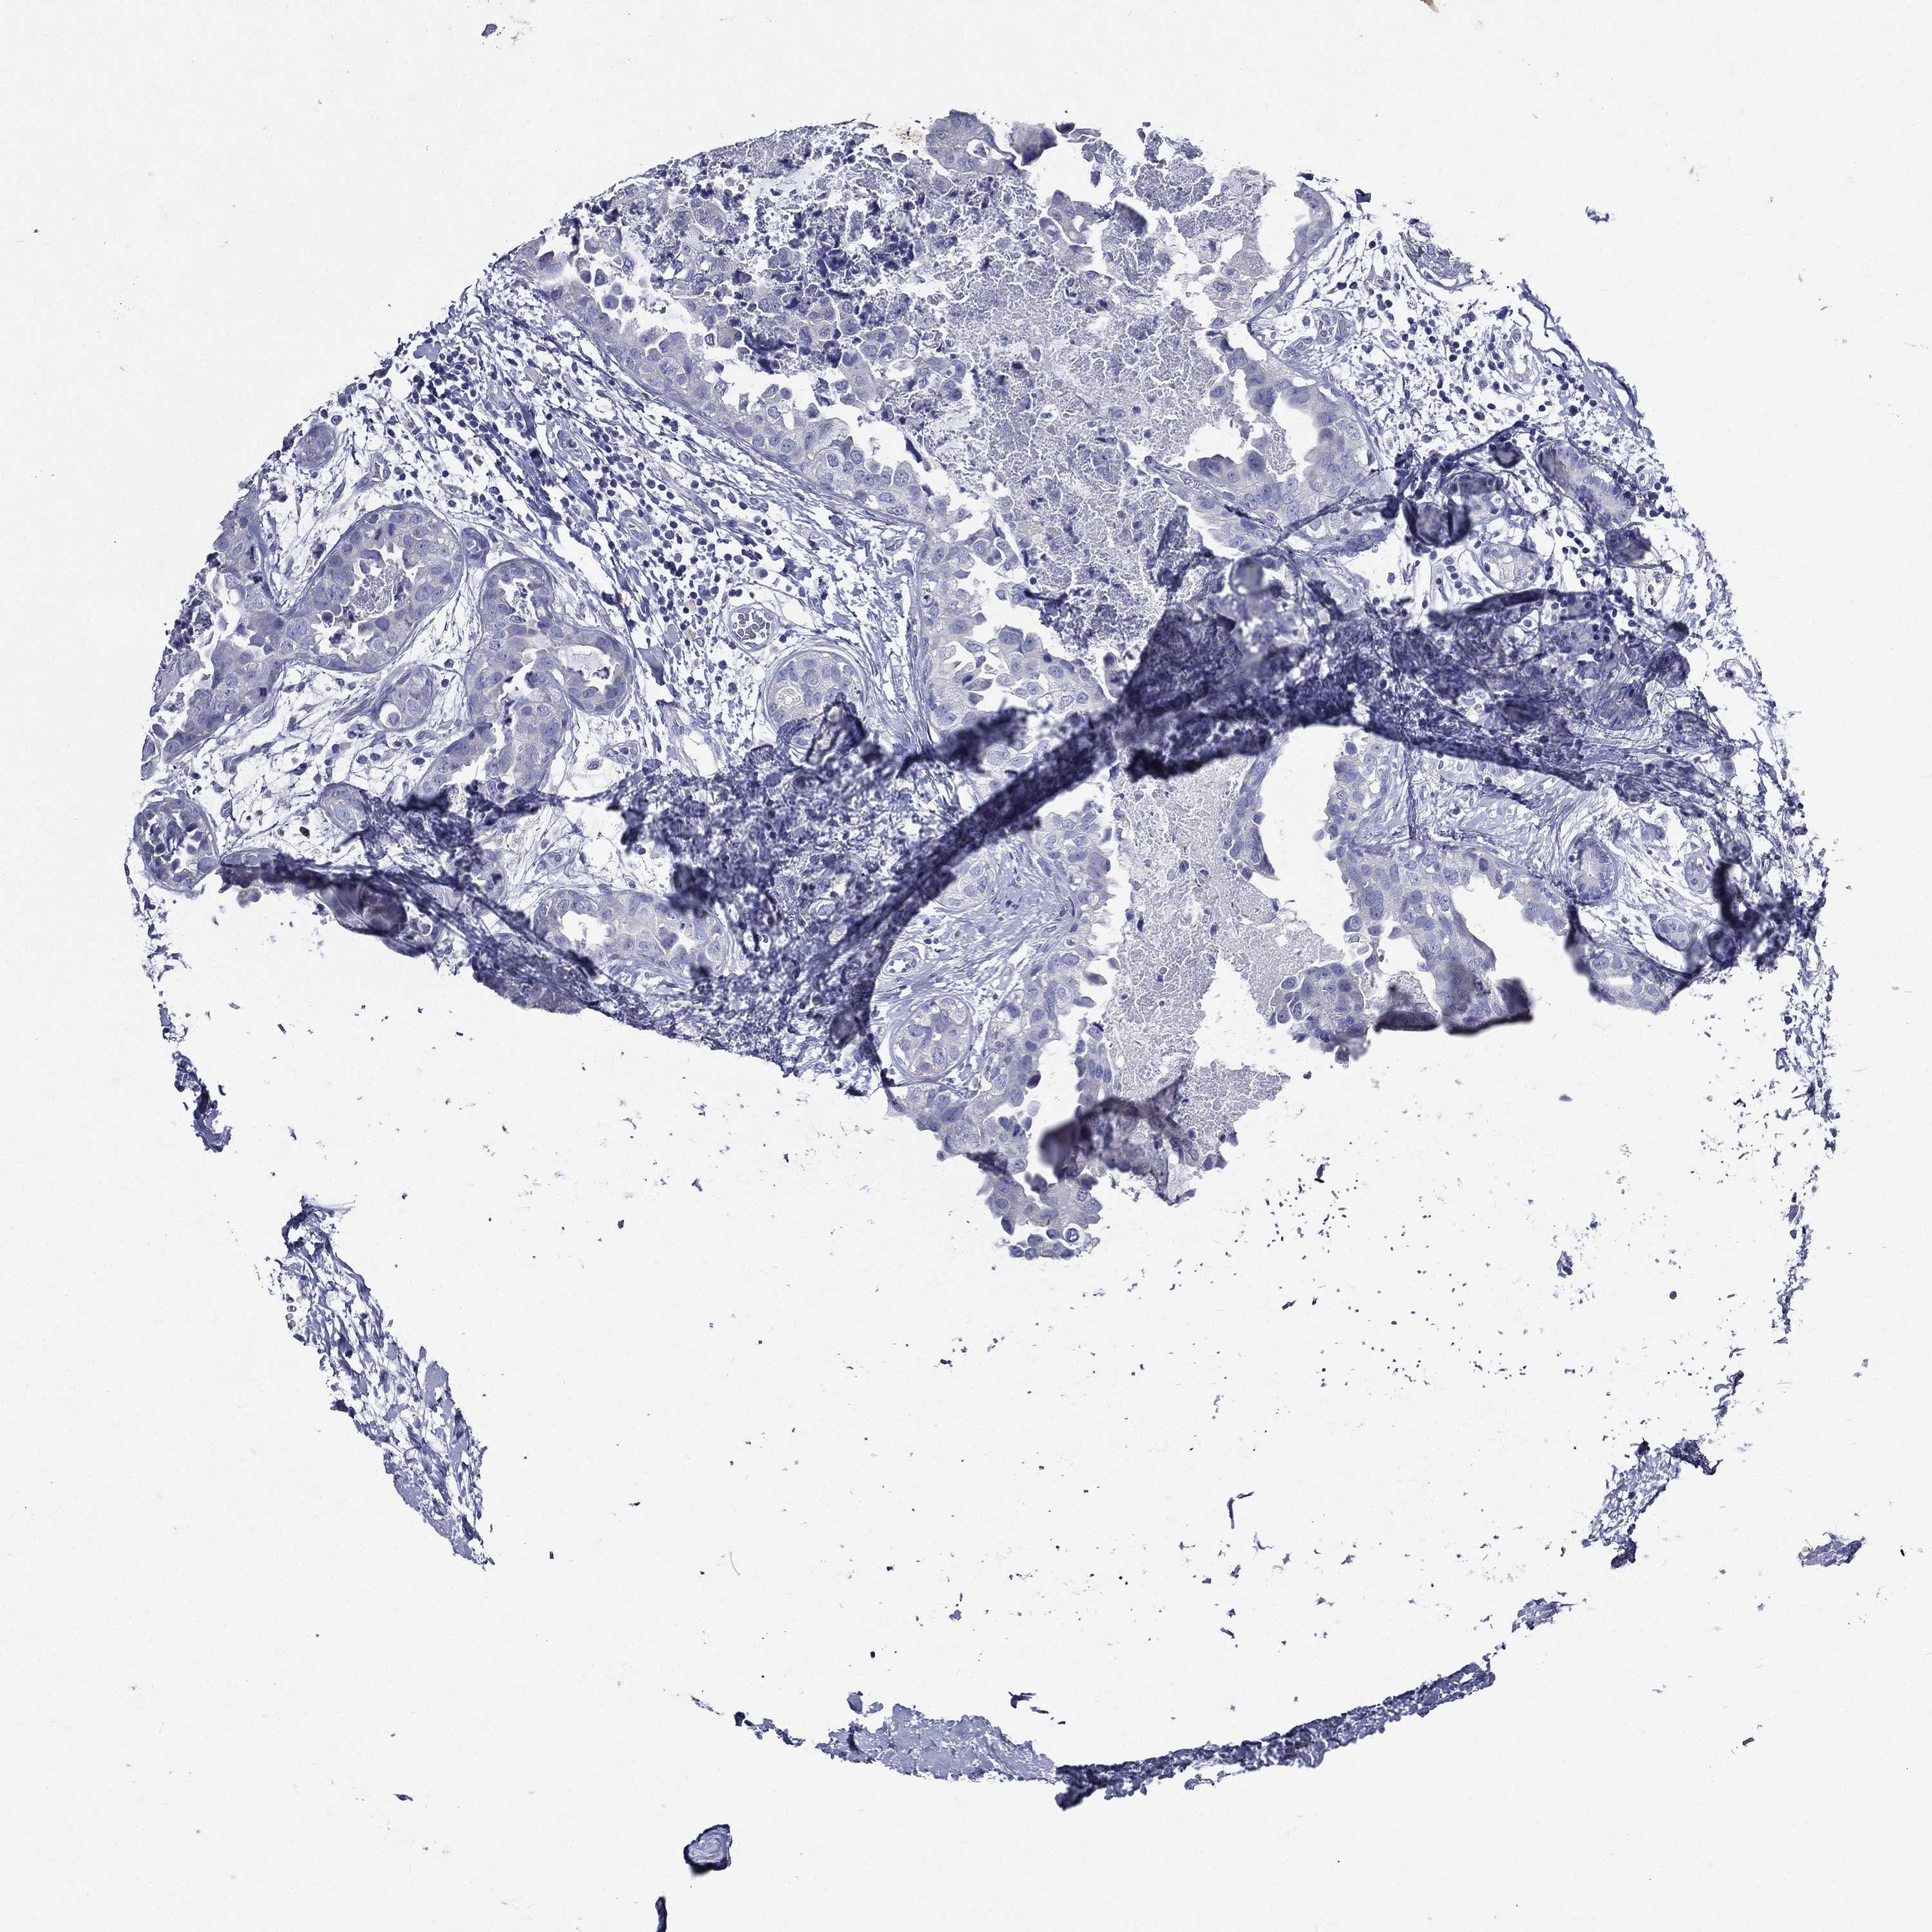

CANCER BREAST CANCER Show tissue menu

BRCA TCGA BRCA VALIDATION PROTEIN EXPRESSION